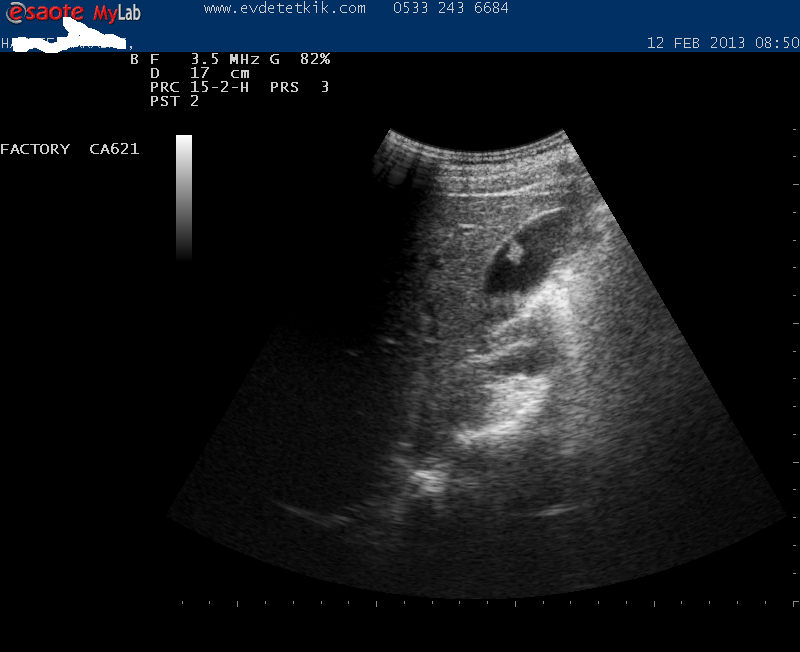

Hizmetimizden görüntüler